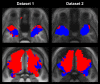

Group probability maps for the two clusters and two datasets in dataset-specific DARTEL space.

Three-dimensional rendering of group maximum probability maps in dataset-specific DARTEL space, thresholded at p = 0.3 and seen from a frontal, slightly elevated angle. The deep cluster 1 is shown in blue, and the superficial cluster 2 in red.

Group maximum probability maps of binary images that indicate whether any target voxel had relatively stronger connections to one or the other seed cluster, as determined by the clustering algorithm. Target voxels that have stronger connections to the deep cluster 1 are shown in blue; target voxels that connect more strongly to the superficial cluster 2 are red.